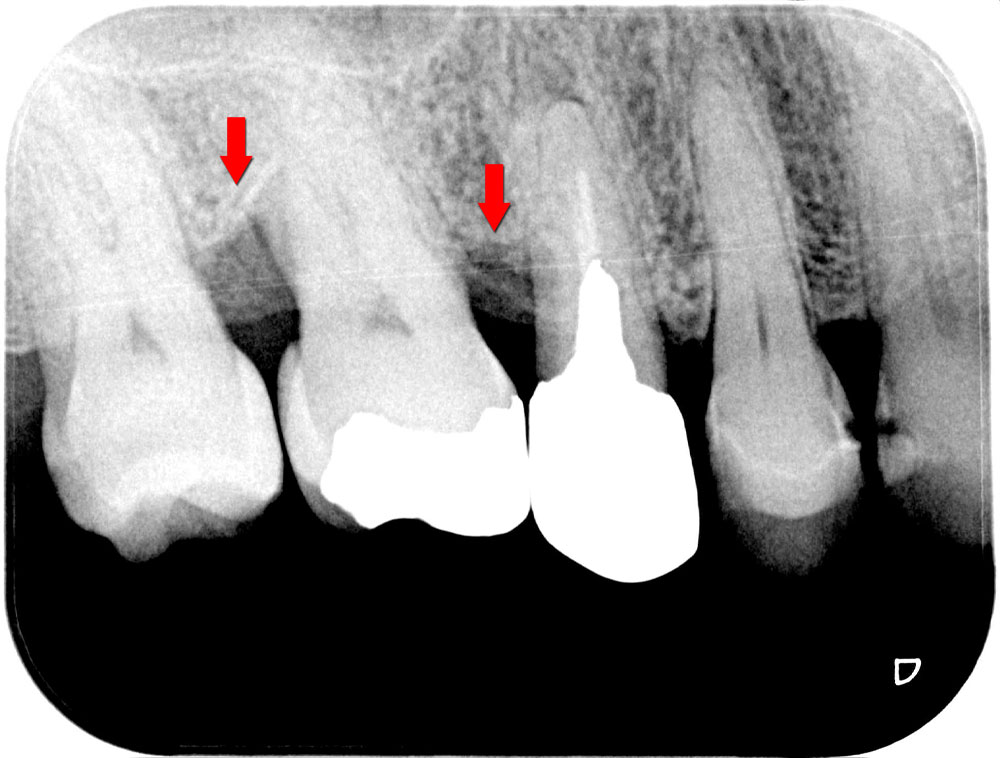

歯周再生治療前

歯周再生手術の終了約1年後のレントゲン写真です。失われていた骨の再生とともに歯槽硬線(↓部)が確認され歯周再生治療の効果を評価・確認しました。慢性的な歯周病の治療とともに、歯を支える顎の骨、歯槽硬線(白線)の再生により歯のぐらつきも改善され患者さんにも、ご満足頂きました。